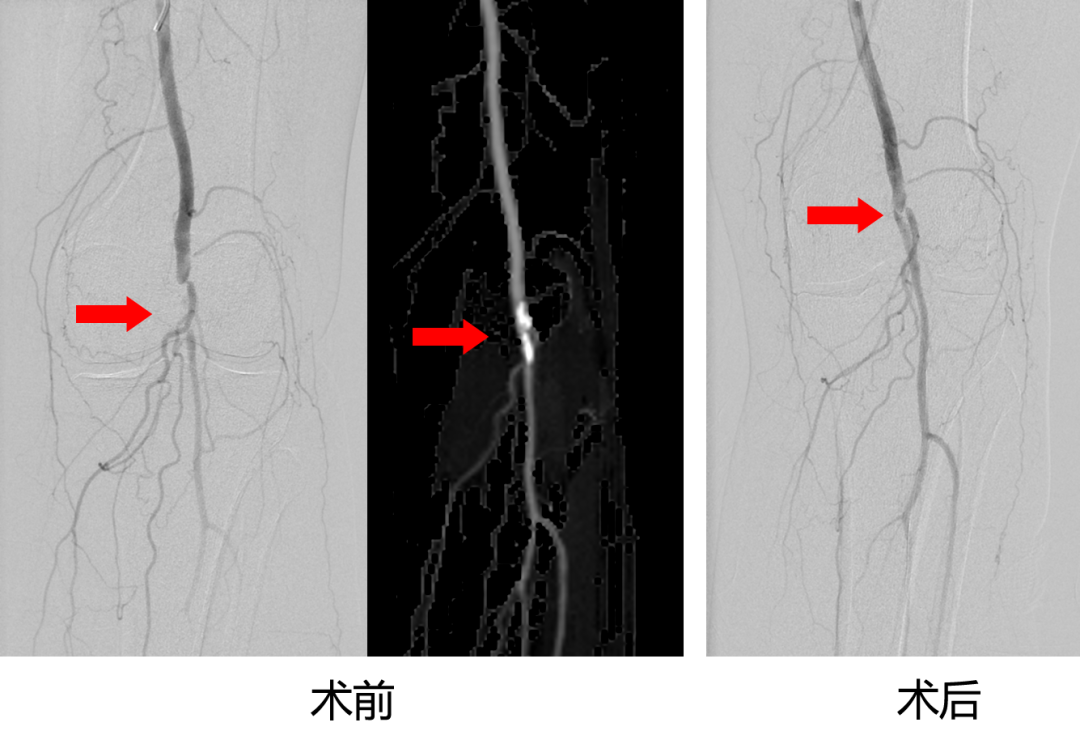

王奶奶左腿的病痛已经快成为她的一块“心病”,两个月以来一直四处奔波就医,可总不见好。直到慕名来到荆州一医介入血管外科蔡杰副主任医师的诊室,王奶奶终于得到了最合适的手术方案:

蔡主任先通过局麻下的血管介入手术,用球囊扩张打通堵塞的腘动脉,恢复腿部供血;针对难愈的烫伤伤口,由尚春波医生做清创术+VSD负压引流,术后由尚医生和邓彩云护士为王奶奶细致换药直至愈合。